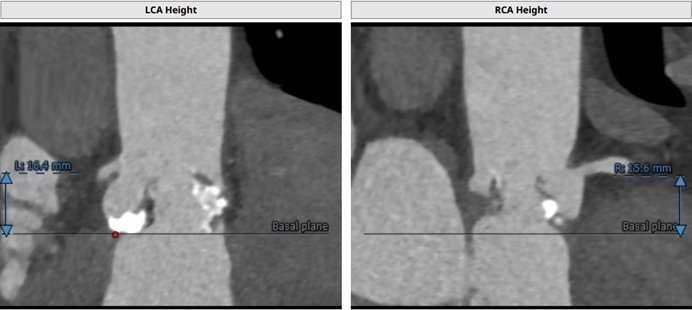

左冠开口高度:16.4 mm;右冠开口高度:15.6 mm